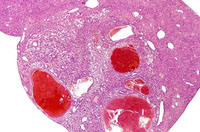

This hemangiosarcoma is well demarcated from the normal hepatic parenchyma; sharp demarcation is an unusual feature of hemangiosarcomas. Large blood-filled lakes are apparent. Higher magnification shows bands of spindle-shaped endothelial cells with attendant destruction of hepatocytes, proliferation of plump endothelial cells, and atrophy of hepatocytes.